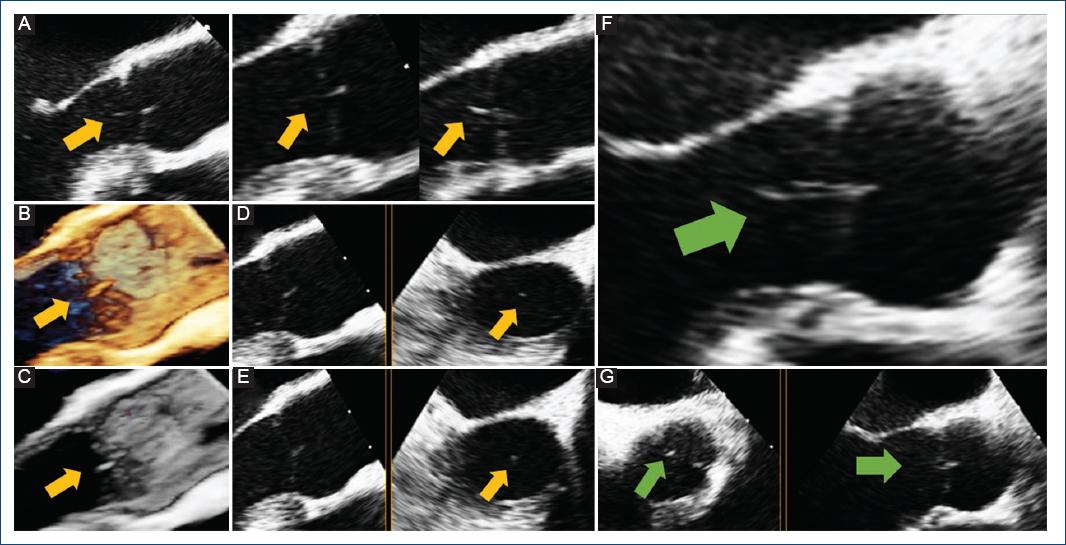

Figure 1 TEE shows Lambl’s excrescence on the aortic valve. Initial TEE (yellow arrow): A: mid-esophageal long axis view depicting a filamentous structure attached to the ventricle surface of the aortic valve; B and C: 3-D reconstruction; D and E: mid-esophageal long axis view in X-plane mode demonstrating the mobile structure in the left ventricular outflow tract. Follow-up TEE, 6 months later, showing no change in the linear mobile structure (green arrow): F: mid-esophageal long-axis view and G: mid-esophageal aortic valve short-axis view in X-plane mode. TEE: transesophageal echocardiogram.

A 29-year-old female with systemic lupus erythematosus was admitted due to persistent fever. Imaging studies and transthoracic echocardiography (TTE) were non-diagnostic for infectious foci. Salmonella Typhi was detected in three separate blood cultures, and an intravenous antibiotic was prescribed; however, the fever persisted and the blood cultures remained positive. Transesophageal echocardiography (TEE) revealed a low-density, thin, hypermobile, filiform lesion on the ventricular surface of the aortic valve, consistent with Lambl’s excrescence (LE) (Fig. 1A-E). Despite the TEE findings, the infectious disease department switched antibiotics, alleviating symptoms and resolving the fever. On the 14th day, blood cultures were negative, whereas follow-up TEE revealed no change in the filamentous structure. The patient was discharged symptom-free and completed 6 weeks of oral antibiotics without recurrence of fever. A 6-month follow-up TEE revealed no changes in the mobile structure or evidence of valvular disease (Fig. 1F and G).